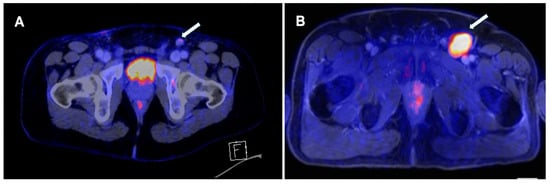

Palpable lymphadenopathy warrants prompt evaluation, as the risk of metastasis is high (45–80%) [4]. Although the early treatment of lymph node involvement has been shown to positively impact survival, the presence of clinically nodal disease at diagnosis does not warrant an immediate ILND since approximately 50% of patients present with inflammatory swelling instead of metastatic spread [4,24]. PET/CT demonstrates a strong diagnostic performance in this context, as shown in Figure 2.

Figure 2. (A). A 37-year-old man with stage T2 penile squamous cell carcinoma. Imaging with 18FDG PET/CT shows one 12 mm, SUVmean 2 suspect left inguinal lymph node (Arrow). Histology revealed a metastasis of PeCa without extracapsular extension. (B). A 61-year-old man with stage T1 penile squamous cell carcinoma. Imaging with 18FDG-PET/MR shows one 40 × 26 mm SUVmax 7 positive left inguinal lymph node. Histology revealed a metastasis of PeCa without extracapsular extension.